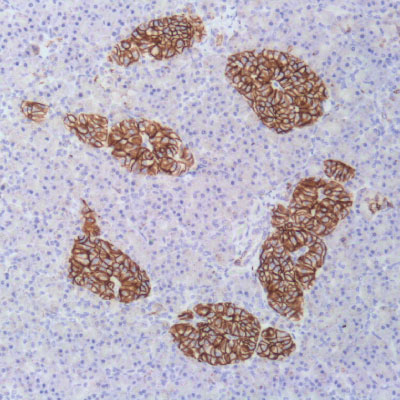

Immunohistochemistry integrates a set of methodologies that use antibodies as specific reagents capable of identifying and establishing specific links with tissue constituents that function as antigens.

Established bindings can be visualized under microscopic observation, due to the labeling of antibodies that cause color development whenever antigen-antibody complexes are formed.

​Vitro Turkey Diagnostics, through its exclusive representation of Master Diagnostica in Turkey, sells antibodies and equipment for immunohistochemical diagnosis (IHC), offering a wide panel of primary antibodies (more than 300 references), as well as universal and high-quality detection systems. sensitivity, based on micropolymer technology for in vitro diagnostics.

With the main objective of providing innovative and top quality antibodies for immunohistochemical diagnosis, we work daily to be informed of the problems and needs of the market, in order to be able to offer our customers the most innovative antibodies with total quality assurance.

Top quality antibodies for immunohistochemical diagnosis. More than 300 references.

Universal and high-quality detection systems. Sensitivity, based on micropolymer technology for in vitro diagnostics.